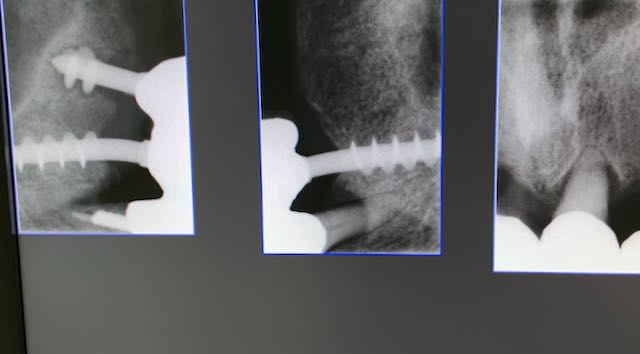

No. of existing implants: 3     Date/number of interventions: in 1993 3 implants in area 14   24   25

Implant type: Tramonte     No. Implants inserted: 2       Welding: No      Dental area: 21   23

Intraoral Rx app: Vix win       CT scan: No      Extraction situation: immediate post extraction implants        Density according to Misch: D2

Operator1:  Dr. Bellini     Operator 2: Dr. Bazzoli      Drill sequence: only lanceolate      Tap sequence: only diam. 4 mm.